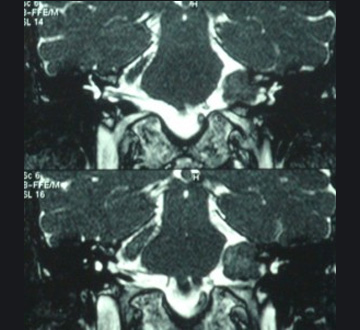

تومور در فضای بین مغز و گوش که زاویه پلی مخچه نامیده می شود، ایجاد می شود. آکوستیک نورما جزء تومورهای خوش خیم است اما خطر این تومور به دلیل رشد آن در فضای حساس و فشار آوردن آن به ساختارهای حیاتی مانند اعصاب جمجمه، مغز و ساقه مغز است. شایع ترین نشانه تومور شامل کاهش شنوائی در گوش مبتلا، وزوز گوش و عدم تعادل می باشد. برای به دست آوردن بهترین نتیجه، تشخیص صحیح به منظور انتخاب بهترین روش درمان در این مشکل است. برای تشخیص نورینوم آکوستیک ام آر آی توصیه می شود. این روش تصویر برداری نه تنها به تشخیص کمک می کند بلکه می کند وسعت و عوارض احتمالی مانند هیدروسفالی را مشخص می کند.

نمونه های زیر MRI پزشک متخصصی است که توسط اصغری جراحی شده اند: